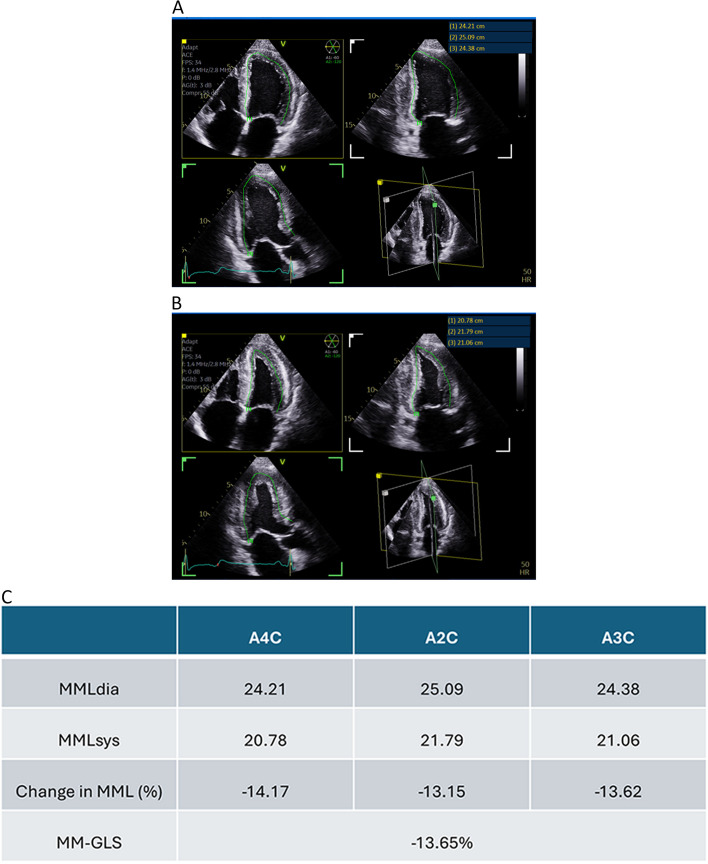

Background: Global longitudinal strain (GLS) is a useful marker for the echocardiographic evaluation of left ventricular (LV) systolic dysfunction. Presently GLS is derived from speckle tracking of LV images, but speckle tracking software is not always available. We seek to determine if manually measured GLS (MM-GLS) by assessing mid-myocardial lengths can be a reliable alternative to speckle tracking GLS (ST-GLS).

Methods: Transthoracic echocardiogram images of a tertiary hospital in Australia were retrospectively analyzed to study the relationships between ST-GLS, MM-GLS, and LV ejection fraction (LVEF). We further evaluated the impact of image quality and regional wall motion abnormalities on those relationships.

Results: Echocardiography studies from 154 patients were included (female sex, 36%; mean age, 61.7 ± 14.8 years). The average LVEF was 51.3% ± 11.3% and the average ST-GLS was 16.7 ± 3.8. MM-GLS strongly correlated with ST-GLS (intraclass correlation coefficient, 0.986; P < 0.001) and with LVEF regardless of the presence of regional wall motion abnormalities. If using GLS cutoff of more than 18% as normal, 97.5% of studies with normal ST-GLS had normal MM-GLS. If using GLS cutoff as less than 16% as abnormal, 95.5% of studies with abnormal ST-GLS had abnormal MM-GLS. There was no case with ST-GLS > 18% and MM-GLS < 16%, nor were there any case in with ST-GLS < 16% and MM-GLS > 18%.

Conclusions: MM-GLS correlates strongly with ST-GLS. If ST-GLS cannot be accurately assessed, MM-GLS may be a useful alternative to provide GLS values in both clinical and research studies.